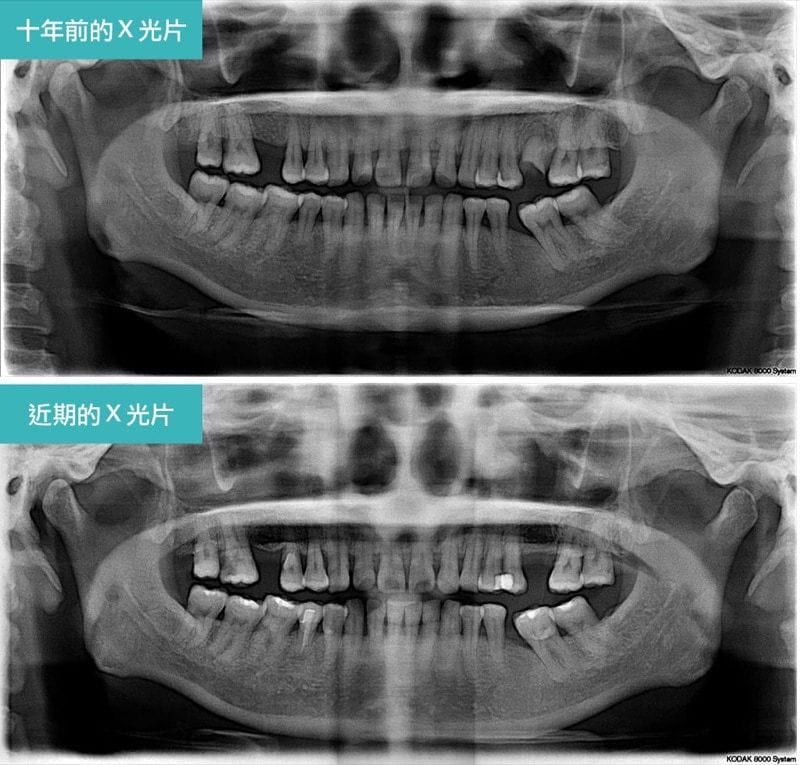

圖示:全口嚴重牙周病,治療前的口腔與牙齒局部X光照